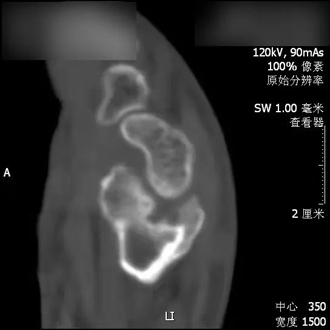

患者桡骨远端畸形愈合

患者老刘,曾于去年不幸发生意外,导致其左腕关节桡骨远端粉碎骨折,关节面受累明显,桡骨远端严重塌陷。未经石膏保守治疗,最终桡骨远端发生畸形愈合。拆除石膏后,虽然经过漫长的康复锻炼,但仍留有明显的功能受限,而且关节疼痛难耐,生活质量受到严重影响。